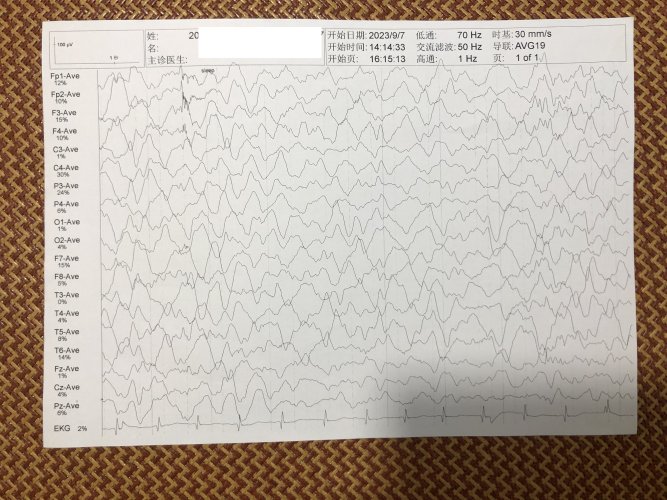

反馈下情况,孩子在国内的医院已经进行过一轮全面检测,没发现什么问题,但是现象是存在的。医生也没什么办法。医生说核磁共振和脑电图没问题,我们也不是很看得懂,各位如果懂的,请指点一下。另外进行了部分基因检测,没发现异常。下一步,我们国庆后打算去更权威的医院去碰碰运气。谢谢各位!